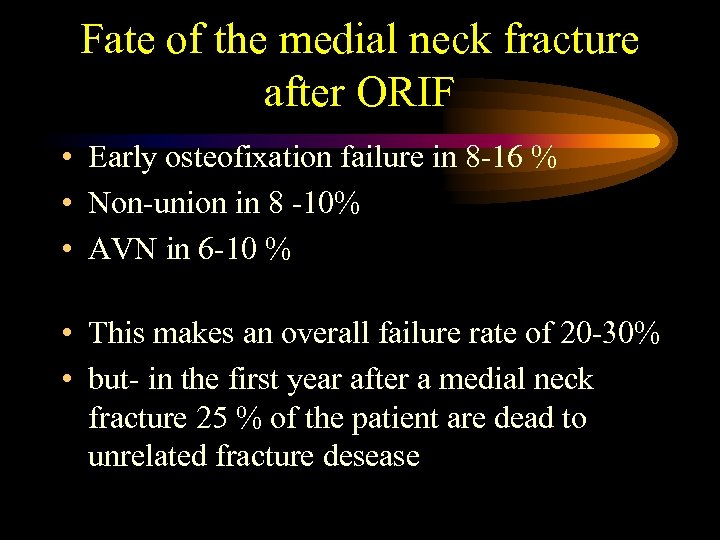

Fate of the medial neck fracture after ORIF • Early osteofixation failure in 8 -16 % • Non-union in 8 -10% • AVN in 6 -10 % • This makes an overall failure rate of 20 -30% • but- in the first year after a medial neck fracture 25 % of the patient are dead to unrelated fracture desease

Fate of the medial neck fracture after ORIF • Early osteofixation failure in 8 -16 % • Non-union in 8 -10% • AVN in 6 -10 % • This makes an overall failure rate of 20 -30% • but- in the first year after a medial neck fracture 25 % of the patient are dead to unrelated fracture desease